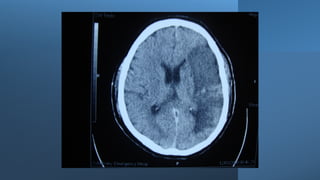

Hemiparesis with facial weakness: brain CT scan or brain MRI, with or

NB: Urgent non-contrast brain CT scan is the most suitable imaging

Paresis, where? Hemiparesis withfacial weakness: brain CT scan or brain MRI, with or without contrast. Hemiparesis without facial weakness: Brain/upper cervical MRI, with or without contrast. NB: Urgent non-contrast brain CT scan is the most suitable imaging modality in patients with acute hemiparesis because of its availability in Emergency Departments (usually), and it is rapid (the period of the test is very brief (compared to MRI). Drawback: poor visualization of posterior fossa structures because of boney artifacts, except in posterior fossa hemorrhages. Paraparesis: dorsal spine MRI, with or without contrast or in some cases, brain/cervical MRI (with or without contrast).